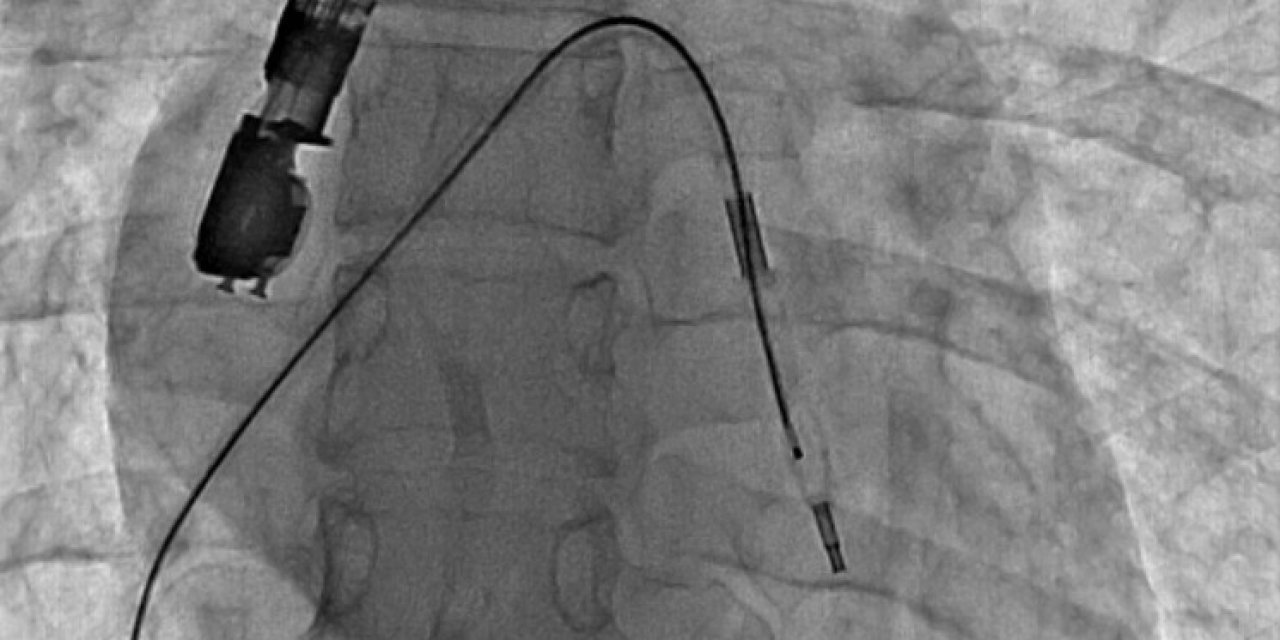

Mitral Balon Operasyonu Adım Adım Kaydedildi

Eskişehir Şehir Hastanesi'nde ilk defa mitral balon operasyonu yapıldı. Operasyon, anjiyografi cihazı ile adım adım kaydedildi.

Eskişehir Şehir Hastanesi'nde ilk defa mitral balon operasyonu yapıldı. Operasyon, anjiyografi cihazı ile adım adım kaydedildi.

Eskişehir Şehir Hastanesi'nde Kardiyoloji Uzmanı Dr. Mehmet Özgeyik ve 4 kişilik ekibi tarafından ilk defa mitral balon operasyonu yapıldı. Türkiye'de az sayıda yapılan kalp kapağı balon işlemiyle yeni anne olmuş genç bir hasta sağlığına kavuştu. Bu sayede hastalar ameliyat olmaktan, ömür boyu kan sulandırıcı ilaçlar kullanmaktan ve metal bir kalp kapağı ile yaşamaktan kurtuluyor.

Gerçekleşen başarılı operasyon hakkında konuşan Kardiyoloji Uzmanı Dr. Mehmet Özgeyik, "Bu işlemi genellikle kalp kapaklarında ciddi darlık olan genç hastaların kişilere uyguluyoruz. Buradaki amacımız ameliyat olmadan, kasıktan küçük iki damar yolu açarak hastalarımızın kapak darlıklarını uzun süreli olarak genişletmeyi hedefliyoruz. Burada 23 yaşında yeni anne olmuş genç bir hastamıza müdahale yaptık. Hastamız ya kapak ameliyatı olacaktı ya da bu işlem sayesinde kapak darlığını aşmayı planlıyorduk. İşlem gayet başarılı oldu. Hastamızın kapak darlığını genişlettik. En azından 10-15 sene boyunca ameliyata gerek kalmadan hastamızı ilaç tedavisiyle takip etmeyi planlıyoruz" diye konuştu.

Cerrahi operasyonlar yerine mitral balon işlemiyle hastaları sağlıklarına kavuşturmak istediklerini aktaran Dr. Özgeyik, "Hastanemizde ilk kez yapılan bir işlem. Bu işlem için uygun hasta bulmak biraz zor oluyor çünkü çok sık yapılan bir işlem değil. Fakat gelecekte hasta portföyümüzün de artması ile birlikte daha sık yapmayı planlıyoruz. En azından hastalarımızı büyük bir cerrahi operasyona vermeden böyle küçük işlemlerle hayat kalitelerini artırmayı planlıyoruz. Hastamız ameliyata gitmiş olsaydı büyük bir operasyon geçirmiş olacaktı. Göğüs bölgesinde büyük bir kesiğe maruz kalacaktı. Aynı zamanda ömür boyu kullanması gereken farklı ilaçlar olacaktı. Hasta kendisine ait olmayan metal bir kapakla yaşamak zorunda kalacaktı. Biz bu işlemde hastaya kasıktan iki tane damar yolu açtık. Hastaya neşter ile kesme işlemi uygulamaktan kurtardık. Ayrıca hastanın hayatı boyunca kullanacağı kan sulandırıcı ilaçları uzunca bir süre ertelemiş olduk. En önemlisi de hastanın kendi kalp kapağını kullanmasını sağlamış olduk ve metal kapak yükünden kurtulmuş oldu" şeklinde konuştu.